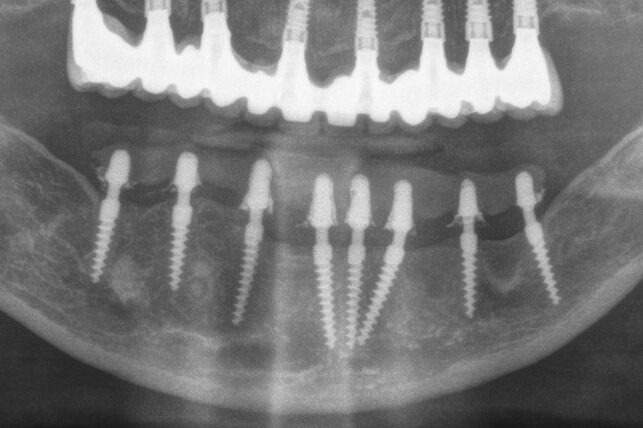

🦷 Antes, durante y después: así mejoró este caso de periimplantitis en 2 años 🦷